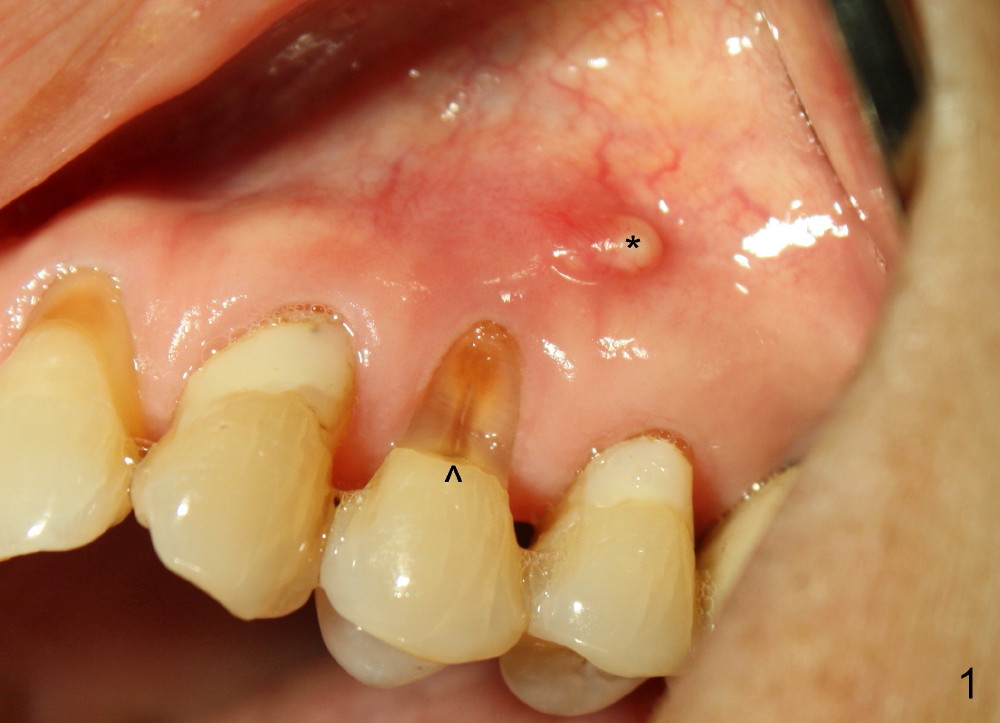

A month later, the fistula disappears (Fig.5). Effort is exerted without success to find the obliterated canal, including increasing access and removing the portion of composite which may block the opening of the canal. RCT is finished. Two months postop, the patient returns for prophy. She remains asymptomatic. There is no recurrent infection. Seven months post RCT, periapical radiolucency seems to have disappeared (Fig.6), whereas the fistula does not recur (Fig.7).